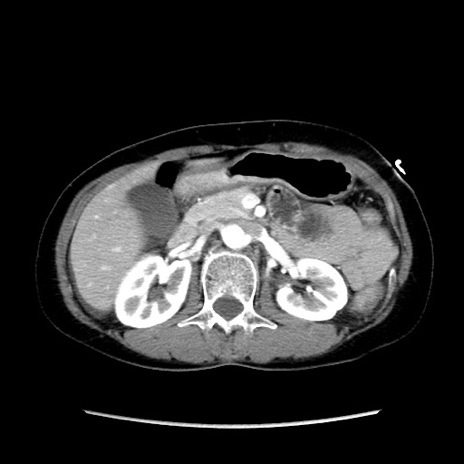

症例32(横断像)

【症例】40歳代 女性

【主訴】上腹部痛、嘔気・嘔吐

【現病歴】約9時間前頃から急に上腹部痛、嘔気、嘔吐が出現。改善しないため救急要請。

【既往歴】子宮頚癌(広汎子宮全摘術、放射線療法)、腸閉塞

【身体所見】腹部:平坦、軟、腸雑音亢進、上腹部を中心に腹部全体に圧痛あり。

【データ】WBC 8400、CRP 0.03